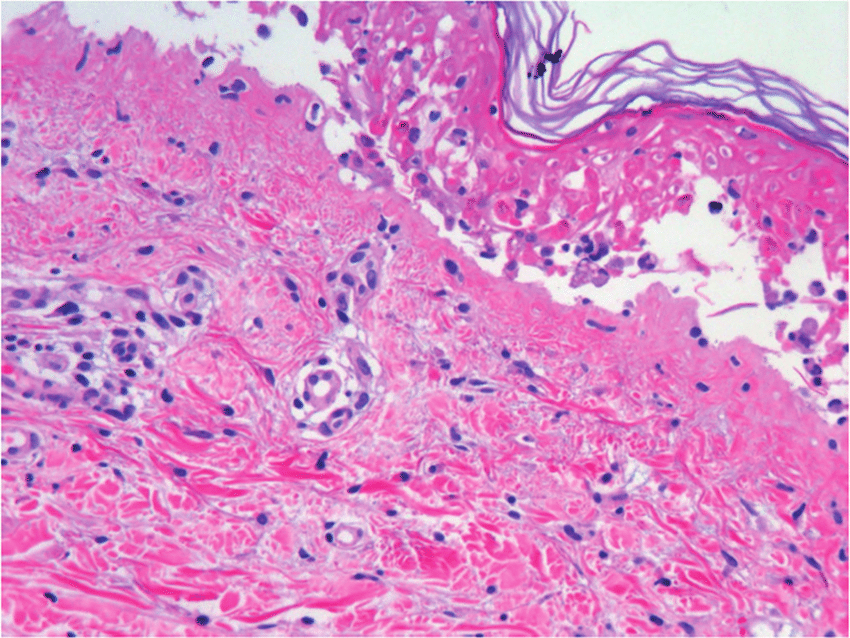

Prevalencia mundial del síndrome de Stevens-Johnson y necrólisis epidérmica tóxica asociados a antibióticos

24 febrero 2023

En esta revisión sistemática y metanálisis de todas las series de casos, los antibióticos se asociaron con más de una cuarta parte de los casos de síndrome de Stevens-Johnson y la necrólisis epidérmica tóxica descritos en todo el mundo. La clase de sulfonamida se asoció con el 32 % de los casos, seguida de las penicilinas (22 %), las cefalosporinas (11 %), las fluoroquinolonas (4 %) y los macrólidos (2 %). Estos hallazgos resaltan la importancia de la administración de antibióticos, la educación y la concientización de los médicos, y sopesar la evaluación de riesgo-beneficio de la elección y duración de los antibióticos. JAMA Dermatol. 15 de febrero de 2023